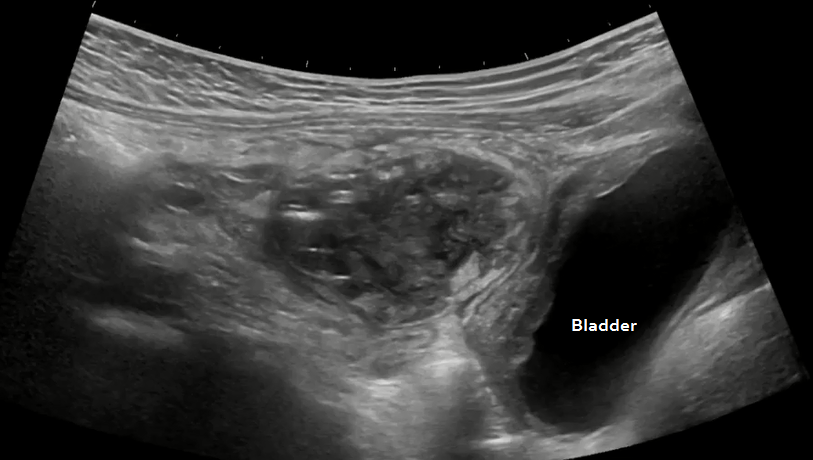

Gynecology